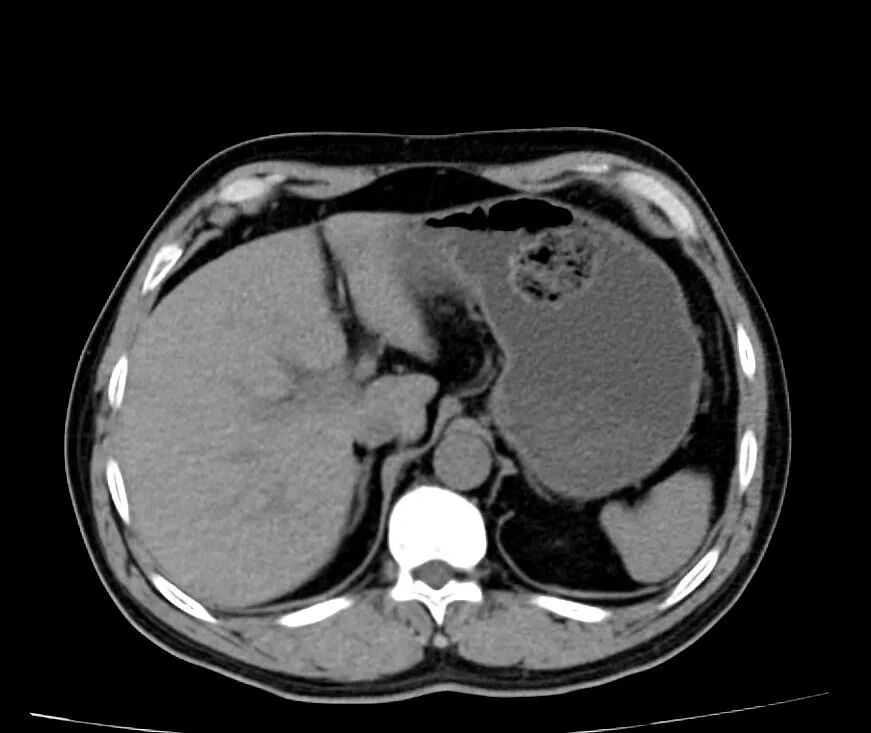

行腹部 CT 检查

发现胃石症而入院

胃石症的诊断

若曾于发病前空腹食用山楂、柿子、黑枣等食物,同时胃镜或者 CT 等影像学检查后,发现胃内结石者,可基本诊断胃石症。